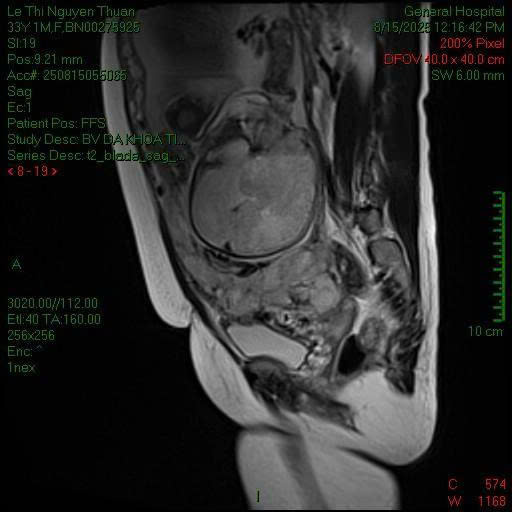

Chụp MRI phát hiện nhau cài răng lược thể percreta.

Bệnh nhân là sản phụ L.T.N.T. (32 tuổi), nhập viện ở tuần thai thứ 38 với chẩn đoán nhau cài răng lược thể Percreta. Đây là tình trạng bánh nhau xuyên qua toàn bộ thành tử cung và xâm lấn vào các cơ quan lân cận như bàng quang.